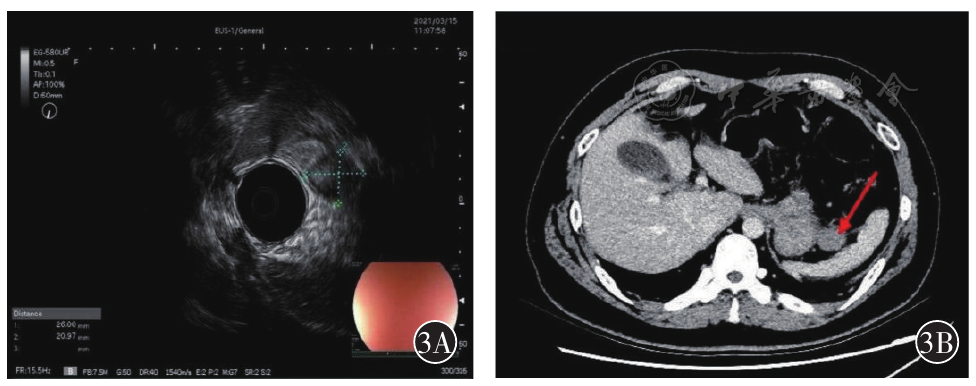

图3 A为超声内镜提示胃体中上部大弯侧圆形低回声病变;B为CT提示脾胃间隙类圆形结节